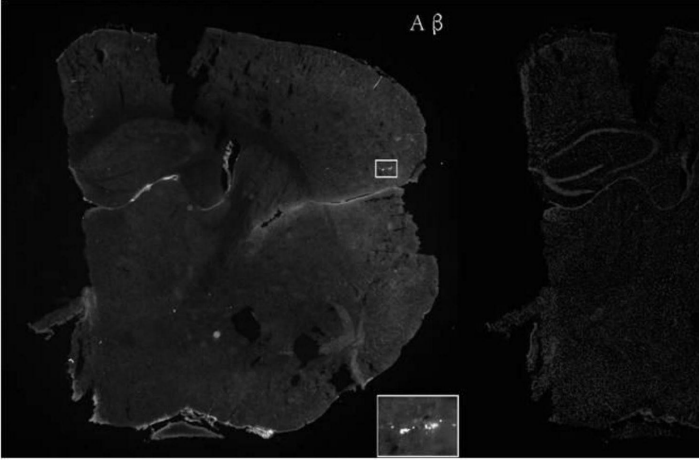

选取若干只4个月大的APP/PS1小鼠并随机分为两组,即实验组和对照组,分别用乳双歧杆菌Probio-M8和生理盐水喂养45天,收集小鼠粪便样本和脑内淀粉样β(Aβ)斑块样本,并进行分析。

实验结果参见图 1和图 2。两组数据对比分析得出,持续灌胃 45天乳双歧杆菌 Probio?M8的小鼠脑中Aβ斑块数量相比灌胃生理盐水组(对照组)有显著减少,其中面积较大的Aβ斑块数量也有所下降。证明了通过口服乳双歧杆菌Probio?M8干预4月龄APP/PS1小鼠可减少阿尔兹海默症特殊病理特征?Aβ斑块数量及面积。

[0015]图1为灌胃生理盐水组的小鼠大脑切片Aβ染色图